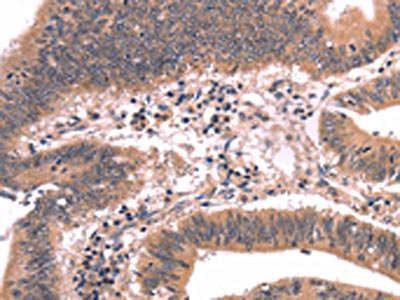

The image on the left is immunohistochemistry of paraffin-embedded Human gastic cancer tissue using CSB-PA077924(FGF22 Antibody) at dilution 1/20, on the right is treated with synthetic peptide. (Original magnification: ×200)

The image on the left is immunohistochemistry of paraffin-embedded Human colon cancer tissue using CSB-PA077924(FGF22 Antibody) at dilution 1/20, on the right is treated with synthetic peptide. (Original magnification: ×200)